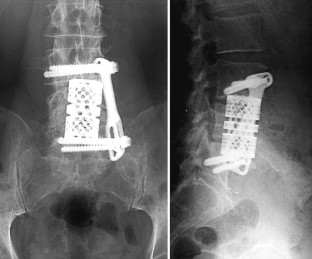

Introduction: The objectives of surgical interventions for tumoral lesions of the spine include the establishment and improvement of tumor-related symptoms. Anterior tumor resection followed by reconstruction indicated if surgical treatment allowed a marginal removal of the tumor or could extend the individual survival rate in combination with adjuvant therapy options. Sufficient re-stabilization depends on adequate anterior column reconstruction. The purpose of this retrospective study was to present our experiences and results after anterior tumor resection followed by reconstruction with the expandable vertebral body replacement device (VBR, Ulrich, Germany) based on clinical application over 4°years. Patients and methods: We carried out an anterior tumor resection followed by reconstruction using an anterior extendable device in 32 patients with different spine tumors between 1996 and 2000. A retrospective evaluation was executed considering the patients medical records and radiological findings. Additionally, a clinical and radiological investigation of still living postoperative patients was carried out. Results: The mean surgical time of all evaluated patients was 317.2 min. The average blood loss was 1,272.5 ml. According to the Tokuhashi score, patients with a postoperative survival time of at least 12 months demonstrated a score value ≥9 points. According to our evaluated patients group metastatic lesions of the spine represented the largest group (78.1%). The average survival rate of this group amounted to 18.4 months postoperatively. Considering primary tumors the average survival rate at the time of last re-examination amounted to 34.8 months postoperatively. Preoperative neurological pathologies were present in 12 patients (Frankel stage C--D). During the postoperative monitoring period 58.3% of the patients demonstrated an improvement in initial neurological findings. There were no intraoperative complications or perioperative deaths. Implant dislocations were not observed. Conclusion: On account of the underlying, the anterior tumor resection with supplementary instrumentation represented a sufficient procedure in spinal tumor surgery. Adjuvant therapy can influence the postoperative survival period positively in addition to the surgical procedure. Following anterior tumor resection, extendable vertebral body replacements like the VBR device provide immediate spine stability by excellent defect adaptation. With regard to their intraoperative flexibility, expandable cages are more advantageous in contrast to non-expandable implants or bone grafts.